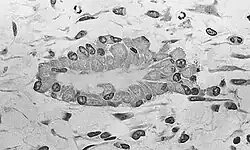

Osteoblastos (do grego ὀστέο-,"osso", e βλαστάνω, "germinar") são as células provenientes das células osteoprogenitoras, são responsáveis pela síntese dos componentes orgânicos da matriz óssea, colágeno, proteoglicanos, glicoproteínas. Os Osteoblastos localizam-se na superfície do osso, formando lâminas de células cuboides a colunares.

Quando estão em intensa atividade sintética, suas formas modificam-se, lembrando um cubo, com citoplasma tornando-se mais basófilo. Em estado pouco ativo tornam-se achatados e a basofilia citoplasmática diminui. Uma vez aprisionado pela matriz óssea recém sintetizada, o osteoblasto recebe o nome de osteócito. A matriz deposita-se em redor da célula e dos seus prolongamentos, formando assim as lacunas e os canalículos (Canais de Havers). Quando os Osteoblastos entram em estado de quiescência, deixam de produzir a matriz, se tornando células de revestimento ósseo.

Microscópio Eletrônico mostra por micrografias que o Osteoblastos apresentam Retículo Endoplasmático Rugoso Abundante e Complexo de Golgi bem desenvolvido. Os Osteoblastos apresentam junções comunicantes em prolongamentos lançados a entrar em contato com Osteoblastos entretanto o número de junções comunicantes entre estas células é muito menor que entre os Osteócitos. Os Prolongamentos dos Osteócitos são mais longos.